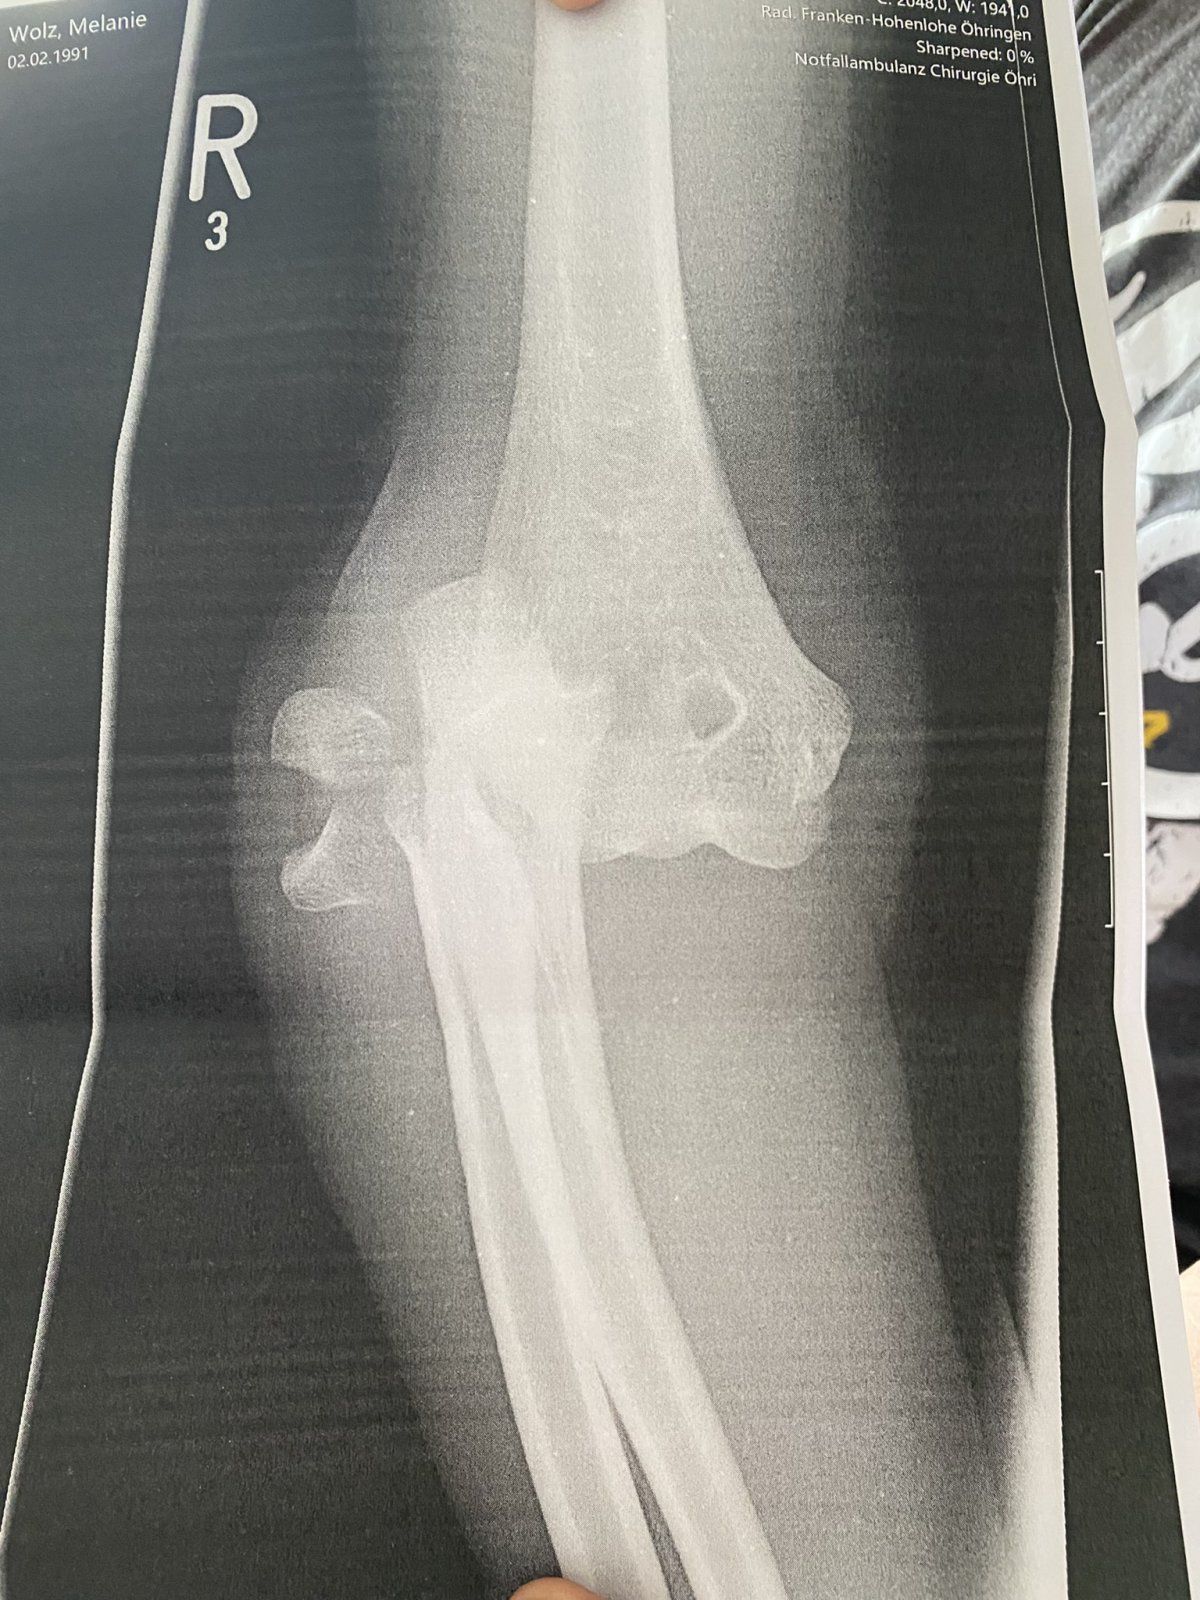

Hallo zusammen, hier scheine ich ja im richtigen Thread zu sein. Vielleicht gibt es Erfahrungswerte zu folgendem Fall. Habe mir das innere Seitenband im Ellenbogen gerissen und einen Muskelfaserriss zugezogen. Am Knochen wurde eine Fisur fest gestellt. Das Ganze ist jetzt 8 Wochen her. Nach einer etwas seltsamen Reise von Arzt zu Arzt hiess es letzendlich es wird nicht operiert. Ich mach 3x die Woche Physio und mach die Übungen fleißig. Allerdings dauert es gefühlt eeewig den Arm wieder in die Streckung und Beugung zu bekommen. Es fehlen in der Streckung noch 25° und schmerzt dann im Gelenk. Und generell wird es nur langsam besser mit der Bewegung. Die Kraft im Arm ist nicht wirklich vorhanden. Nun meine Frage... ist so etwas bei Euch vollständig geheilt. Es kann bei einer konservativen Behandlung zu Instabilität kommen - gibt es da Erfahrungswerte? Gerade im Zusammenhang mit dem Biken und der Haltung auf dem Rad?